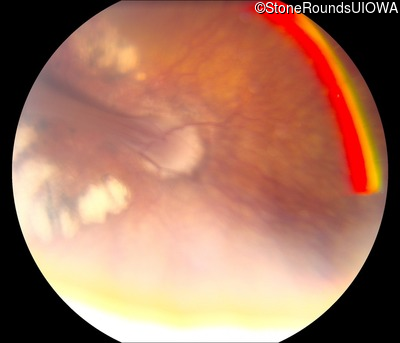

Visit at age: 13 years

Fundus Photography - Left - 20/250

Exemplar